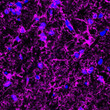

Anti-MBP antibody (STJA0003695)

| Short Description | Chicken polyclonal anti-MBP for use in WB, IHC and ICC in Bovine, Human, Mouse and Rat samples. Datasheet included with dilution recommendations, and related reagents. |

| Applications | WB/IHC/ICC |

| Reactivity | Bovine/Human/Mouse/Rat |